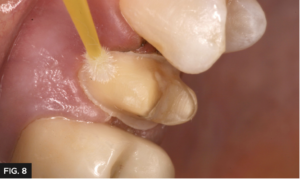

Given the patient’s sensitivity upon biting and to prevent post-operative sensitivity, the preparation was scrubbed with G5™ All-Purpose Desensitizer (Clinician’s Choice®) using a micro brush for 10-15 seconds. (FIG. 8) It is important not to allow the G5 to contact the soft tissue and is recommended to be used sparingly. Provisional composites vary with heat generation, oxygen inhibited layer thickness, strength and polishability.